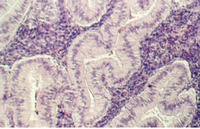

After ovulation, the oocyte is then picked up by the fallopian tube (oviduct) which has fimbria (finger-like processes) extending over each ovary. It becomes simpler as it approaches the uterus. Below is a low magnification view of the fallopian tube in the ampullary region.

This section is taken from the ampulla of the oviduct. Note the elaborately branched mucosal folds projecting into the lumen. The epithelium is simple columnar, although it may appear pseudostratified. The following figure is from your slide 83.